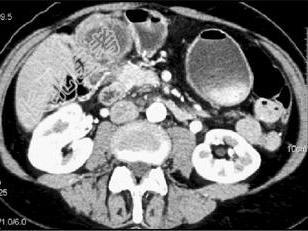

- 单项选择题患者70岁,体重减轻, 结合图像,最可能的诊断是 ( )

A、黑色素瘤转移

B、结肠癌转移

C、肝癌

D、胆囊癌

E、以上都不是